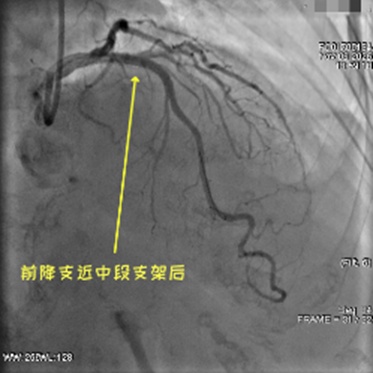

手术当天,导管室内气氛严肃却有序,医护人员各司其职:消毒、穿刺、送导丝,每一个动作都精准娴熟。当冲击波球囊顺利抵达钙化病灶,随着40次平稳的震动,团队成员都屏住了呼吸。

“复查IVUS!”当屏幕上出现新的影像时,所有人都松了口气——原本坚硬的钙化环已明显断裂,道路被成功“拓宽”。紧接着,药物支架顺利植入、扩张、贴壁,一系列操作一气呵成。当“手术成功”的消息传到等候区,卫阿姨的家人紧紧握住医生的手,泪水在眼眶里打转:“谢谢你们,又给了我们一次希望!”